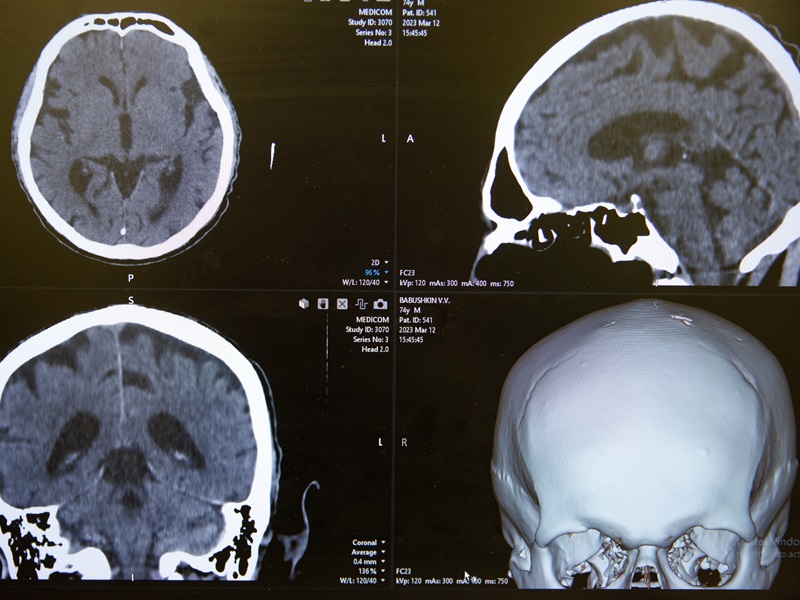

Магнітно-резонансна томографія (МРТ) головного мозку ― це одне з найчастіших досліджень в неврології та нейрохірургії. Зображення головного мозку формується у будь-якій площині без іонізуючого випромінювання та дає змогу виявити анатомічні особливості, патологічні зміни та аномалії мозкових структур та судин (у разі проведення МР-ангіографії).

За необхідності може бути призначена МРТ головного мозку з контрастом. Це дає змогу краще оцінити різницю між нормальними та патологічно зміненими тканинами (за рахунок проникнення контрасту через гематоенцефалічний бар’єр у разі ушкодження останнього патологічного процесу).